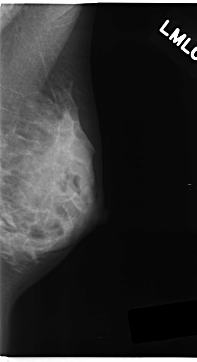

C_0152_1.LEFT_MLO

LEFT_MLO LINES 4704 PIXELS_PER_LINE 2552 BITS_PER_PIXEL 12 RESOLUTION 50 NON_OVERLAY

LESION_TYPE MASS SHAPE LOBULATED MARGINS ILL_DEFINED

ASSESSMENT 5

SUBTLETY 3

PATHOLOGY MALIGNANT